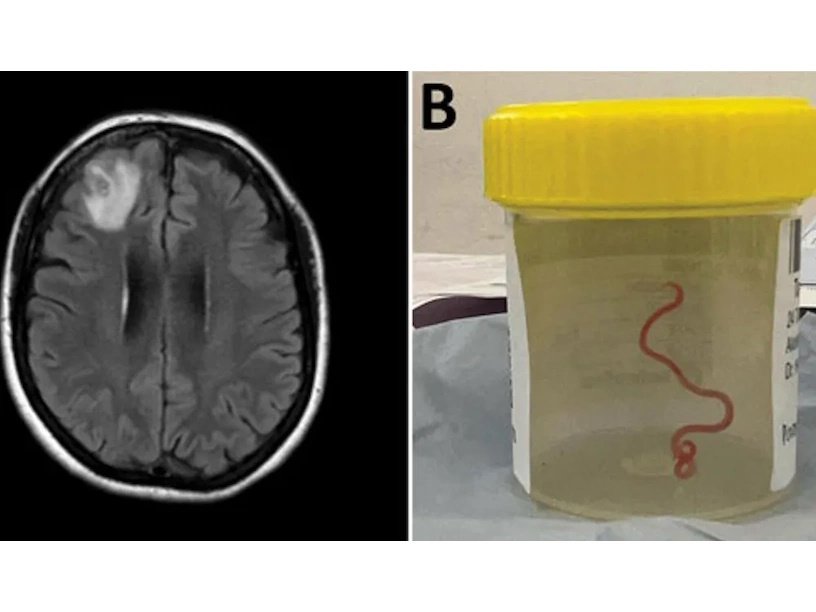

Но в первой половине 2022 года пациентка стала жаловаться на забычивость, и врачи решили провести томографию головного мозга. В результате они обнаружили растущее поражение правой лобной доли. В июне 2022 года была проведена операция. Нейрохирург Хари Прия Банди извлекла из мозга пациентки объект, похожий на струну, который оказался живым извивающимся паразитическим червем красноватого цвета длиной около восьми сантиметров. Хари Прия Банди признает, что это было не только неожиданным, но и несколько выходило за пределы ее зоны комфорта. «Я встречала червей только благодаря своим не очень хорошим навыкам садовода, — говорит она. — Я нахожу их ужасающими и я вообще не имею с ними дела».

Приглашенный для консультации специалист по круглым червям определил, что это Ophidascaris robertsi, который обычно живет в кишечнике ромбических питонов (Morelia spilota). Промежуточными хозяевами паразита служат коалы и сахарные сумчатые летяги, а также другие сумчатые млекопитающие мелкого или среднего размера. Но врачи никогда ранее не обнаруживали его в мозге млекопитающего и никогда не сталкивались с тем, чтобы этот паразит заражал человека.